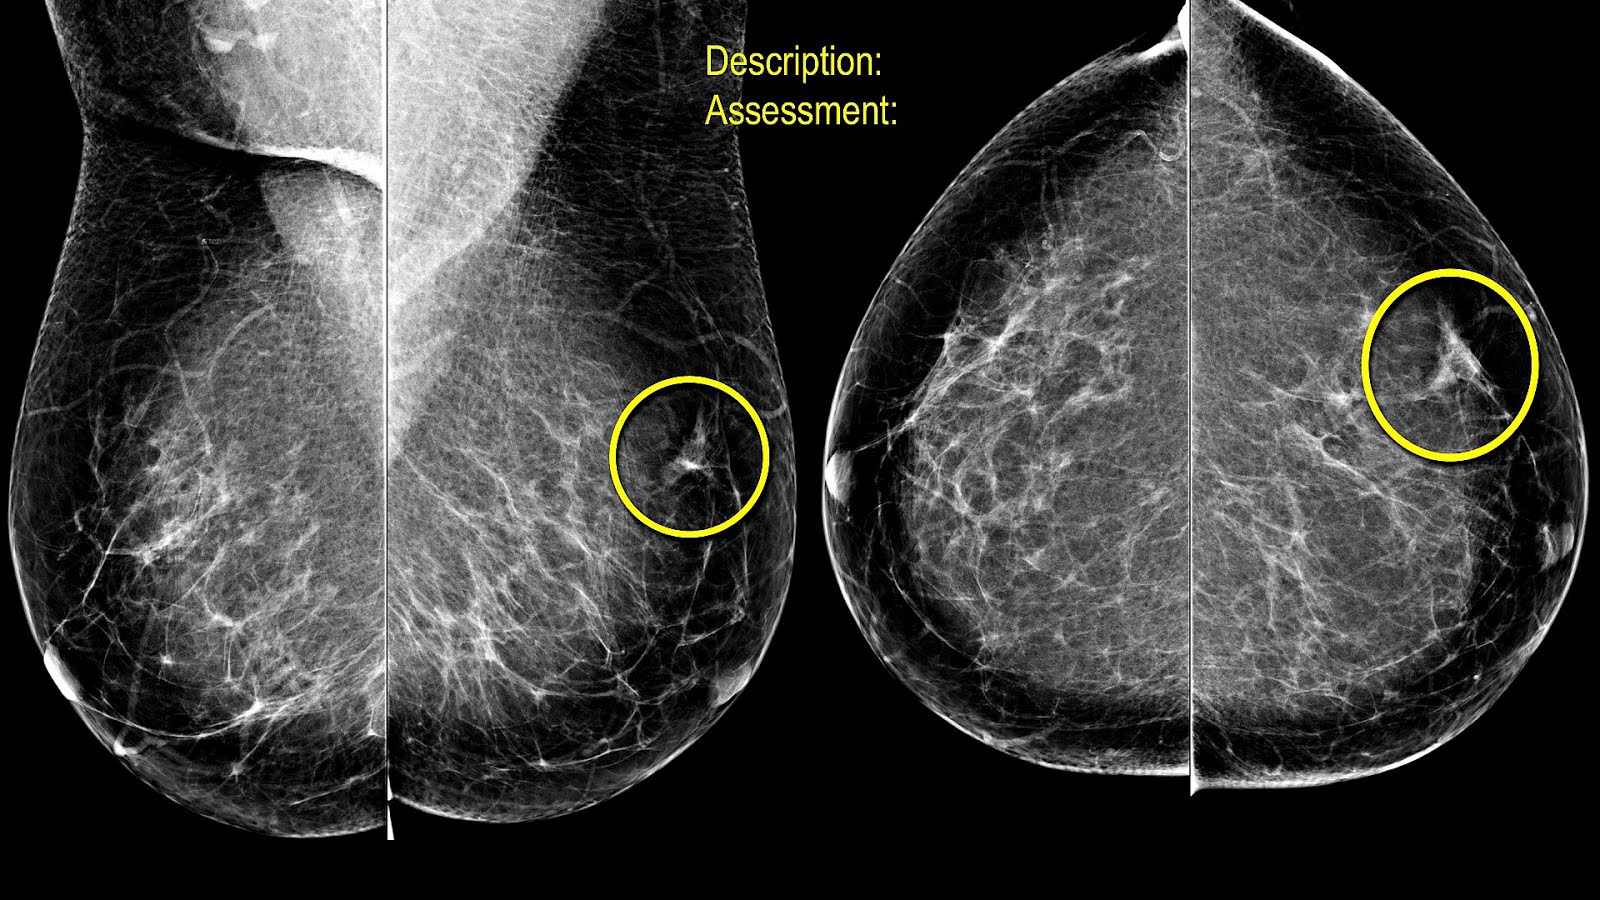

Durante el estudio, cada mama se coloca entre dos placas que la comprimen para obtener imágenes claras del tejido interno. Esta compresión es breve y dura apenas unos segundos, pero puede generar sensación de presión intensa. La finalidad de este paso es reducir la cantidad de radiación necesaria y mejorar la calidad diagnóstica de las imágenes.

Los avances en tecnología médica han permitido el desarrollo de mamógrafos digitales y equipos de mastografía 3D que optimizan la calidad de imagen y reducen el tiempo de exposición, lo cual contribuye a una experiencia más tolerable. Además, muchos centros de imagen cuentan con personal capacitado en brindar atención sensible y empática, lo que disminuye la ansiedad y mejora la colaboración de la paciente durante el estudio.